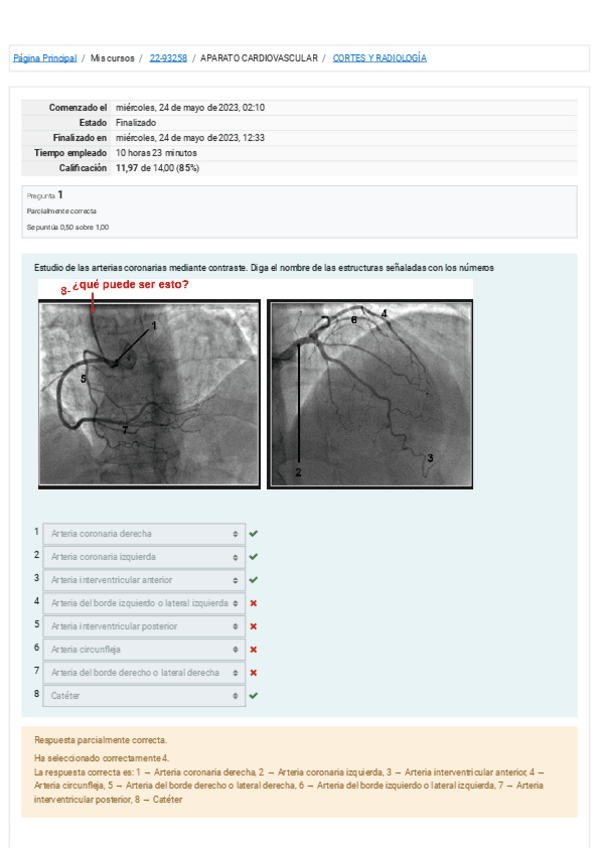

He publicado nuevos practicas de 1º Anatomía Humana I: CORTES-Y-RADIOLOGIA-cardiologia.pdf

14 páginas